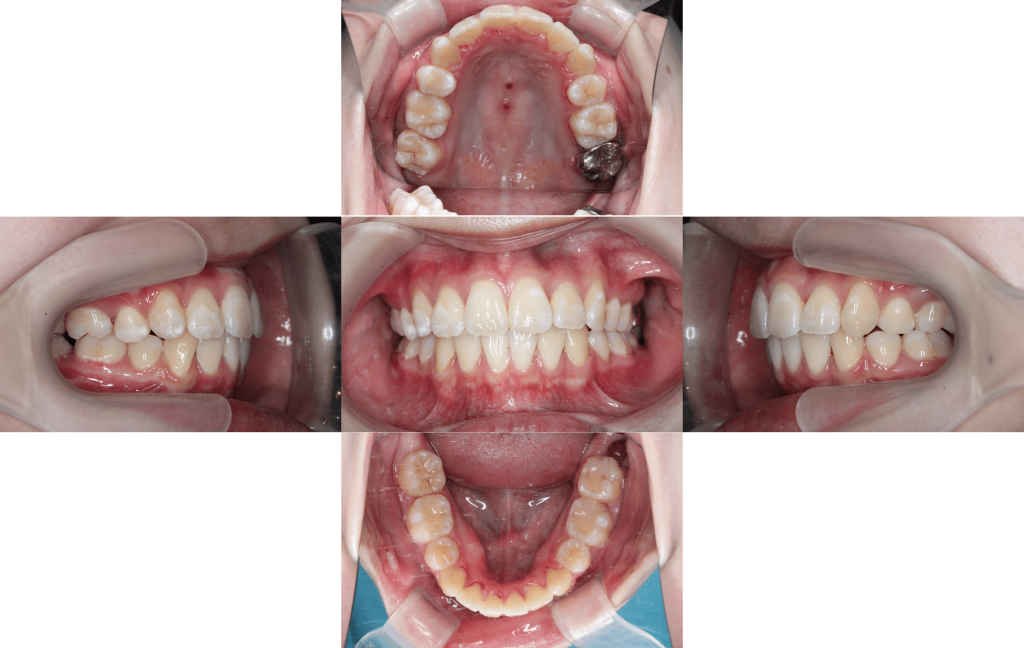

Before

After

初診

装置装着

約6か月後

約1年後

約1年6か月後

約2年後

約2年6か月後

約3年後

年齢層

20代

性別

女性

主訴

・1┴1でっぱり・凸凹な歯並び・Eライン・上下のかみ合わせ

治療費用

¥1,320,000

治療期間

約3年(治療中)

抜歯

上下顎両側第一小臼歯

矯正の装置

マルチブラケット装置(裏側矯正)

副作用、リスク

歯肉退縮,歯根吸収,疼痛,咬合の違和感,装置の違和感,虫歯,歯肉炎